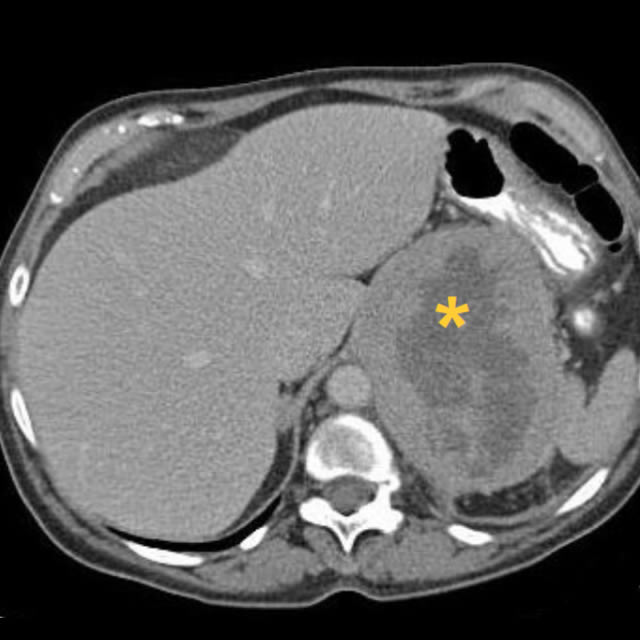

Categorical courses, offering AMA PRA Category 1 Credits™, range from two to five days within the four-week course and provide radiologic-pathologic correlation for both radiology residents and practicing radiologists to show how the underlying pathology of a lesion relates to its imaging appearance.

The mission of these courses is to enable participants to utilize knowledge of how radiology and pathology correlate to improve their diagnostic accuracy in identifying specific diseases, their treatment and potential complications.